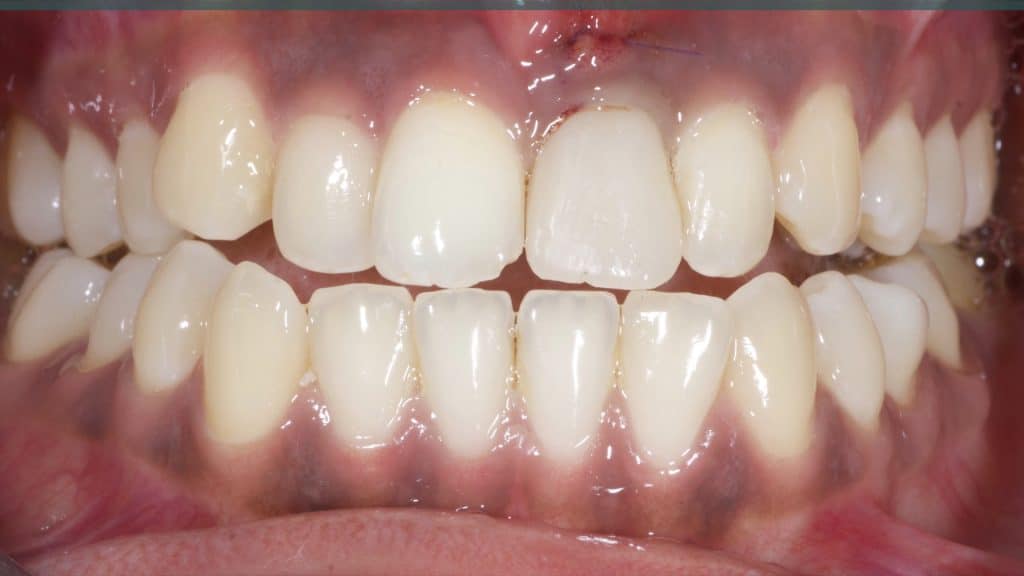

Immediate post-op

Occlusal check